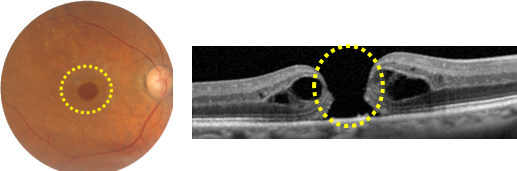

黄斑円孔

黄斑に穴が開き、視力が大きく落ちてしまいます。手術で目の中にガスを入れて穴を押さえつけると、穴がふさがります。穴にガスが当たるように、術後一時的にうつ伏せの姿勢をとります。